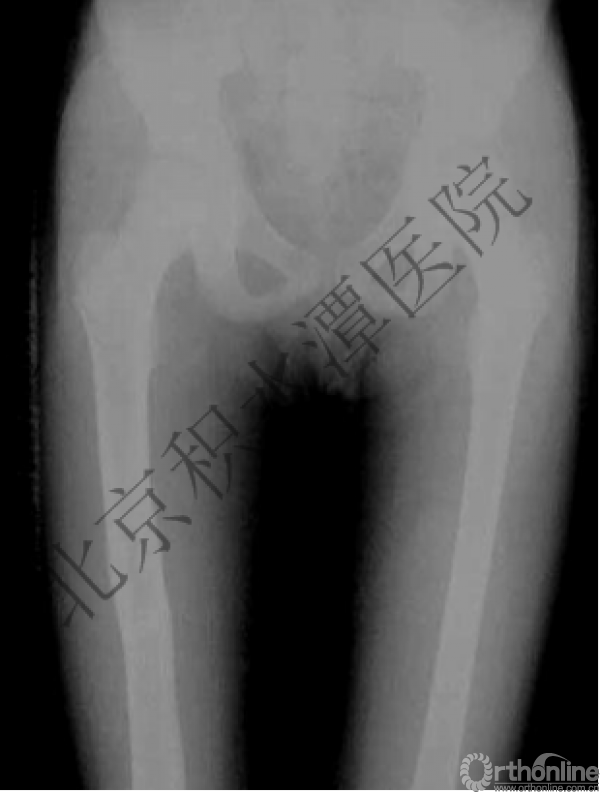

病例分享二

2岁、股骨干骨折,切开+内固定

简单牵引即可!为什么要如此大动干戈?

现实中又是怎样的呢?不知道这属于知识缺乏范畴还是道德品质问题?

匪夷所思!

新生儿股骨干骨折

为什么要手术治疗?

医源性损伤—不愈合!

不具备对儿童骨骼特点的基本了解,不了解儿童骨折的特点,想当然地治疗!